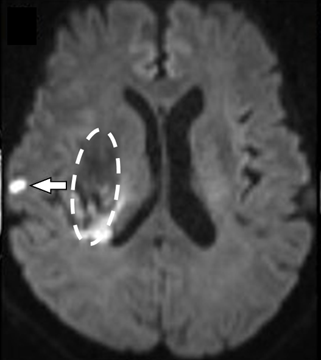

脳出血を発症した時の隠れた小さな脳梗塞

(図1)脳出血(破線囲み部分)を発症した時の“隠れた小さな脳梗塞”(矢印)